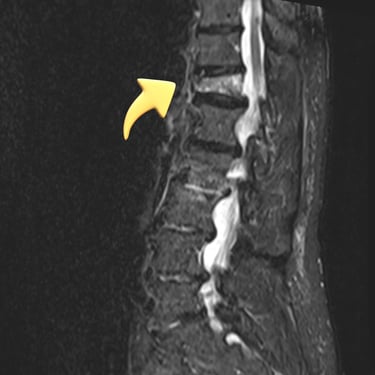

🧠Listesis Lumbar L5–S1 por Fractura Ístmica: Estabilización con FTP y TLIF.

La listesis L5–S1 por fractura ístmica causa inestabilidad y dolor. El tratamiento quirúrgico con FTP y TLIF permite descompresión neural y estabilización vertebral, mejorando la función y calidad de vida.